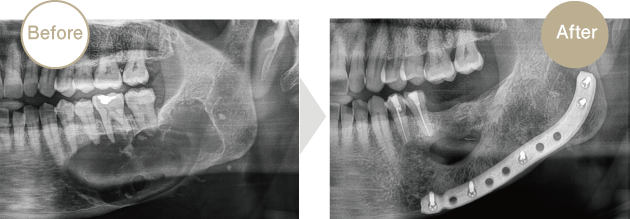

症例.01

歯原性嚢胞

70代男性、左側下顎に巨大な嚢胞形成。病的骨折の可能性を鑑み、チタンプレートで補強したのち摘出しました。神経損傷もなく治癒傾向良好です。